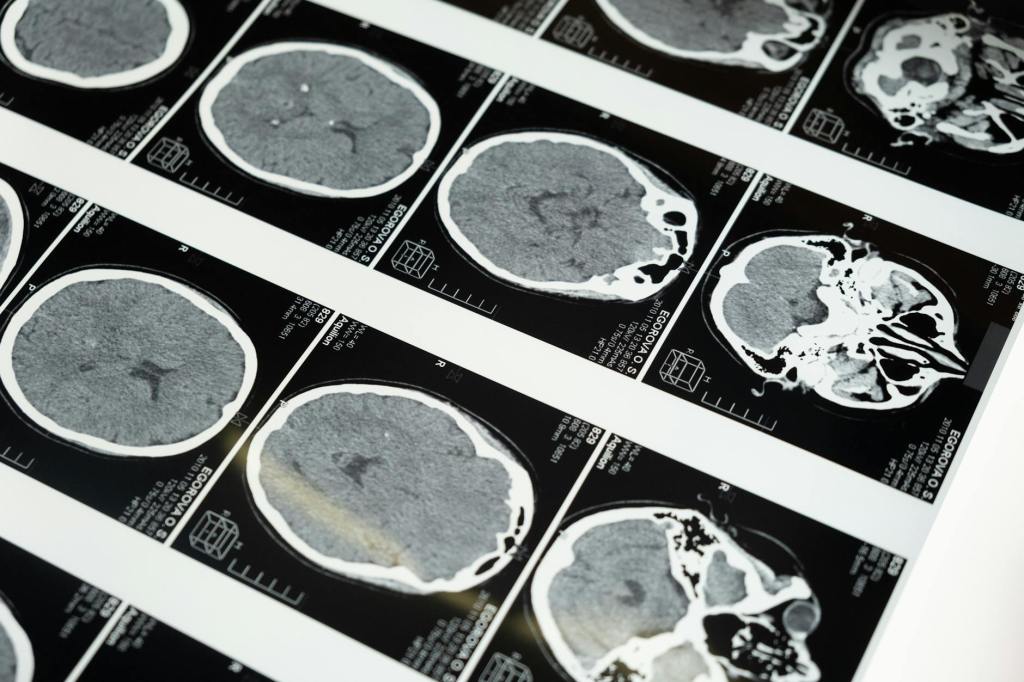

To process everything from the past weeks, I just need to start writing. I want to be able to remember this, so this was that day, from my perspective. 5/31/25 Saturday morning, I woke up around 7 am, which is pretty early for me, but I was working the 9 am-10 pm shift,…

Derek made leaps and bounds within the first 24 hours. His scar is wicked huge. The doctors weren’t very communicative our first or second night at the UIHC. I was disappointed. Granted, I didn’t really know what I was expecting but it was something … more. We’ve all heard “We’re…